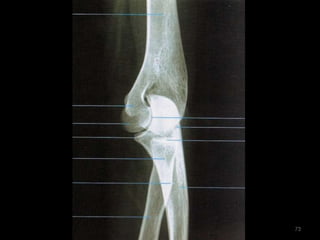

Incidência lateral cotovelo (látero-medial)65

66

67